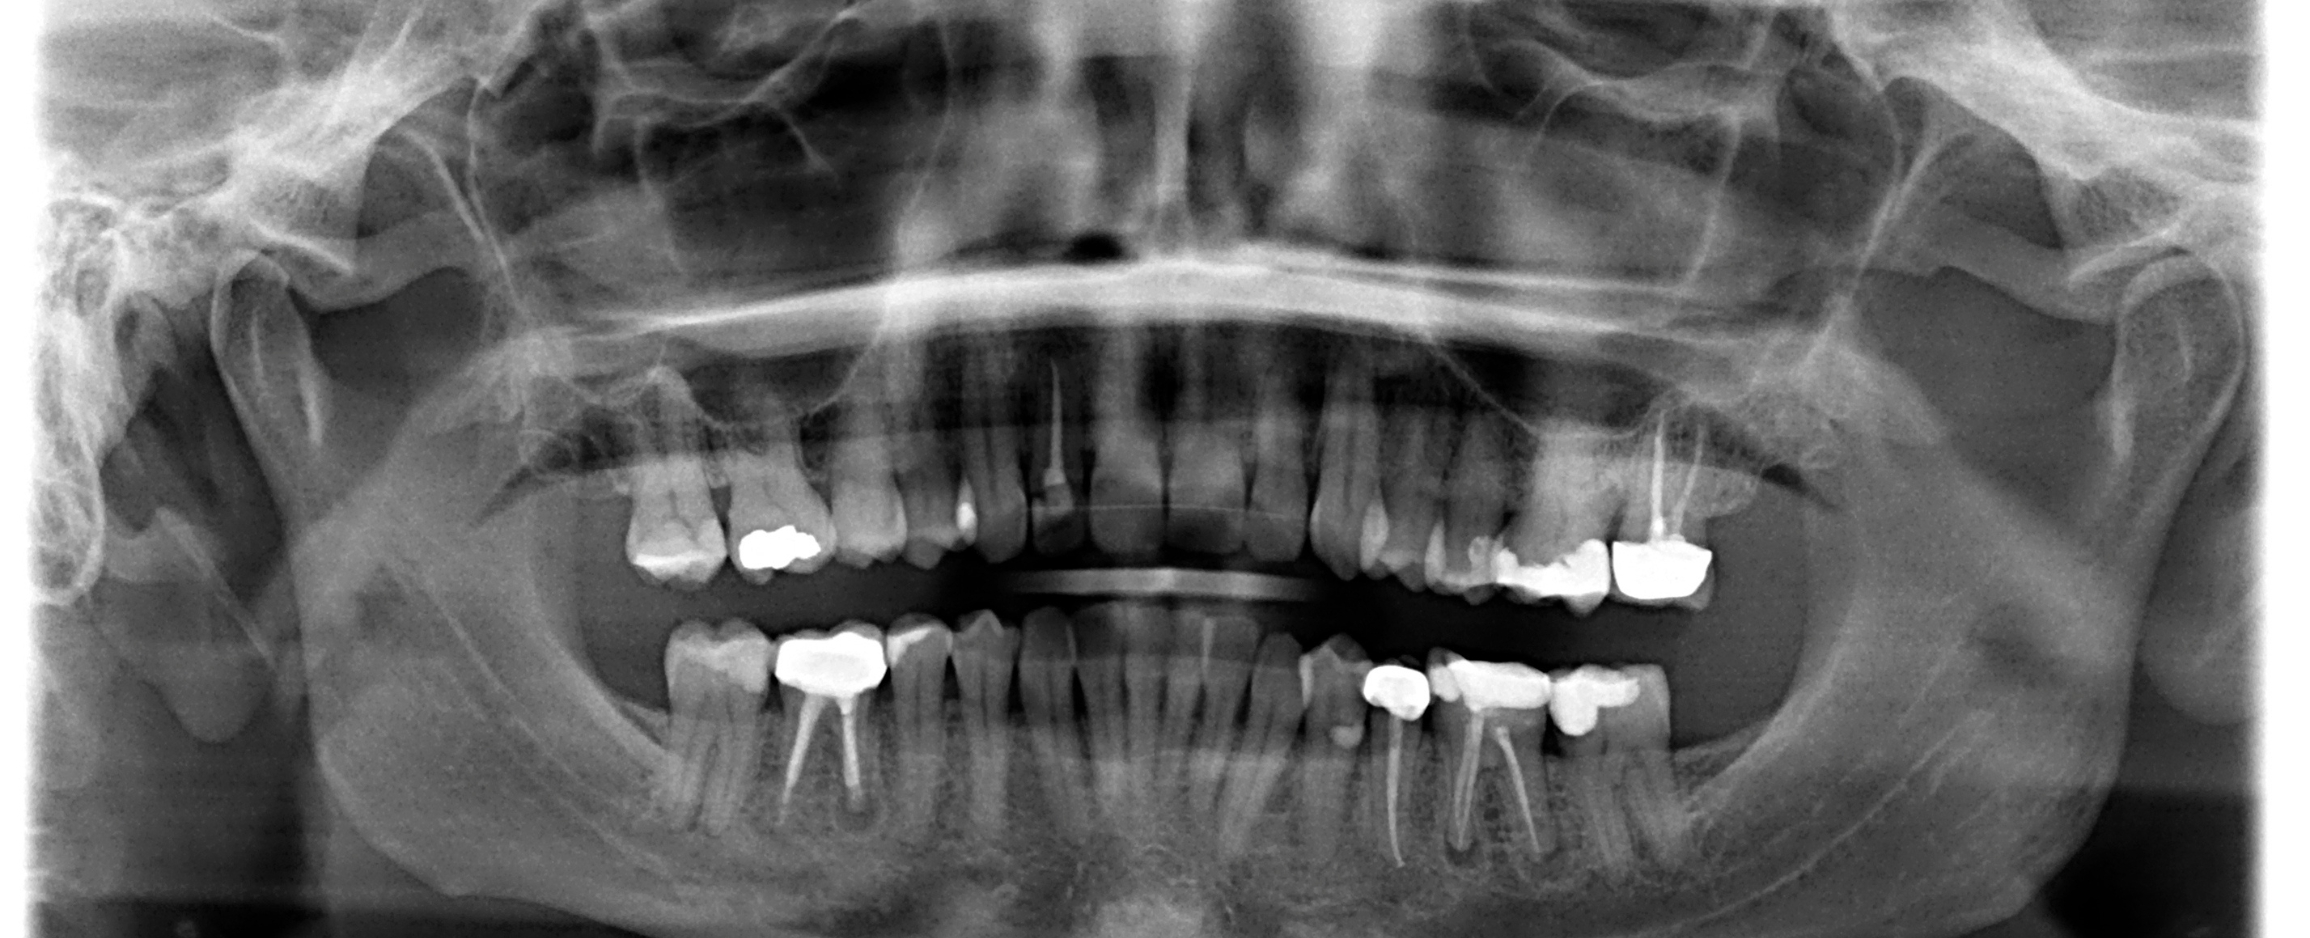

The company’s strong history in X-ray manufacturing, along with a deep dedication to delivering products that exceed the needs of dental professionals, has earned Gendex recognition as a global leader. The Gendex DP-700 gives clinicians dependable image capture of a wide variety of radiographs. These images are valuable for diagnosis and treatment planning of caries, root investigation, orthodontics, implants, and other surgical procedures, as well as patient education in both 2D panoramic and 3D CBCT scans.

The GXDP-700’s panoramic imaging includes a wide variety of projections, including bitewing and TMJ, to expand your radiographic capabilities.

Other projections consist of orthogonals, frontal dentition, and sinus, and most views also allow for the selection of either right or left exposures. With an automated 2D/3D sensor exchange, two sensors that rotate to capture both 3D and panoramic images, clinicians merely press a button to switch from taking 3D images to 2D panoramic projections for a lower targeted dose to the patient.

The Gendex DP700 boasts one of the highest special resolutions on the market today.

With images being captured from a standard 0.3mm (300 microns) to an impressive 0.133 mm of detail. Due to this detail, it opens the imaging up to other areas of dentistry, such as periodontal and endodontic work and not just implants.